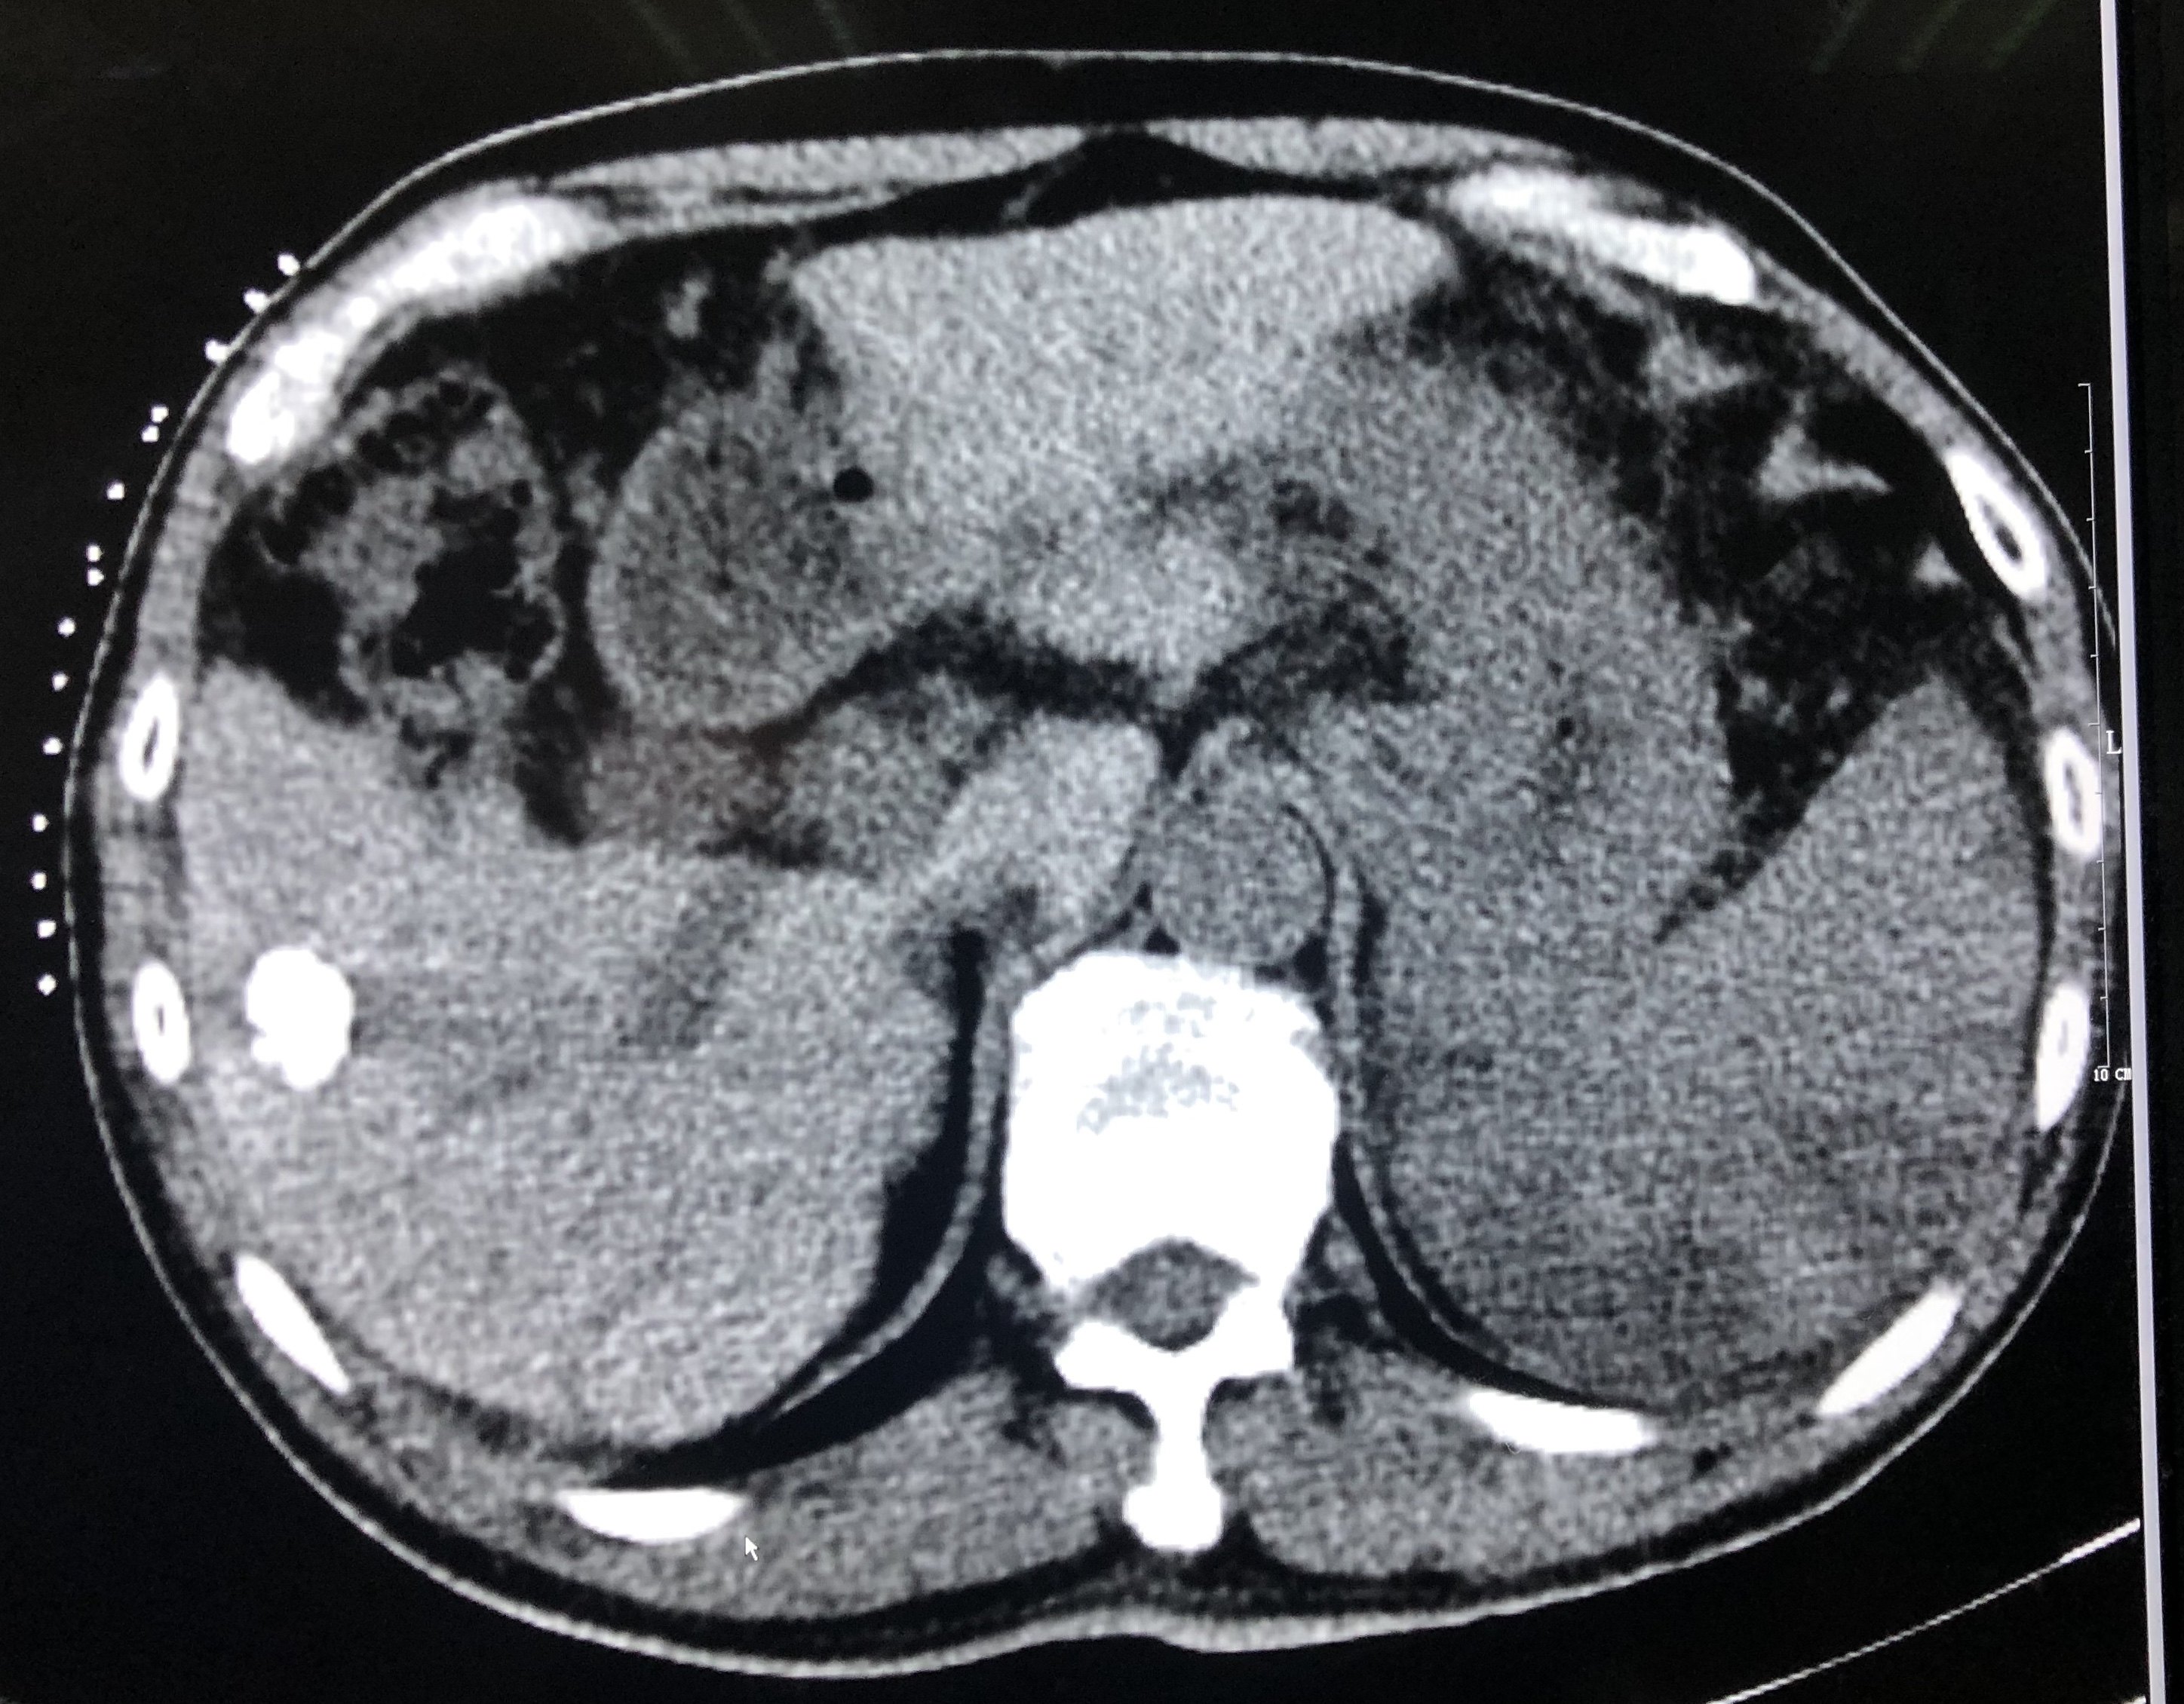

术后右肝肿瘤碘油沉积良好。脾脏少许低密度灶为栓塞后改变。

一月后复查见右肝肿瘤完全灭活。